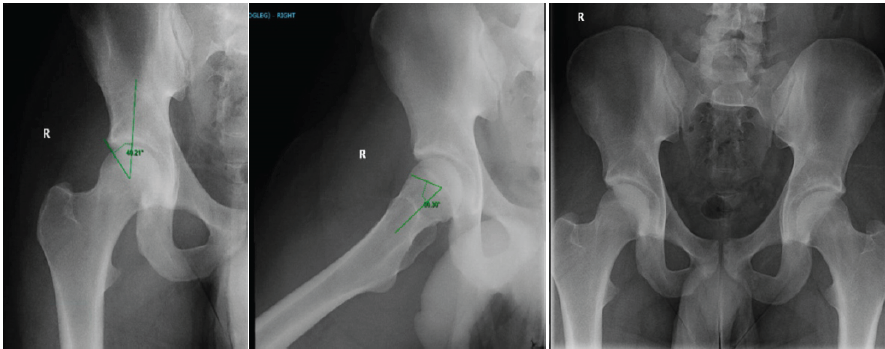

A 20-year-old male Division 1 college offensive lineman with no significant medical history or right hip problems presented with right hip pain after feeling a pop in his right hip while doing a squat. His exam was notable for tenderness over the right hip flexors. Plain radiographs of the hip and pelvis demonstrated femoroacetabular impingement syndrome (FAI) morphology with an alpha angle of 60° and a lateral center edge angle of 40° (Fig. 1).

Figure 1: XR of right hip and pelvis demonstrating femoroacetabular impingement syndrome morphology.